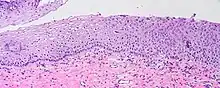

Koilocytes can be visualized microscopically when tissue is collected, fixed, and stained. Though koilocytes can be found in lesions in a number of locations, cervical cytology samples, commonly known as Pap smears, frequently contain koilocytes.[5] In order to visualize koilocytes collected from the cervix, the tissue is stained with the Papanicolaou stain.[5] Another way koilocytes can be visualized is by fixation of tissue with formalin and staining with hematoxylin and eosin, commonly known as H&E.[5] These stains give the cytoplasm and nuclei of cells characteristic colors and allows for visualization of the nuclear enlargement and irregularity, hyperchromasia, and perinuclear halo that are typical of koilocytes.

In LSIL of the cervix, definitive koilocytes are present. In addition, squamous cells commonly display binucleation and mitoses are present, signifying increased cellular division.[7] However, these changes are primarily limited to upper cell layers in the epithelium, no mitoses are found higher than the lower one third of epithelium, and the basal layer of cells remains a discrete layer. This differentiates this lesion from high-grade squamous intraepithelial lesion (HSIL) of the cervix.[7]